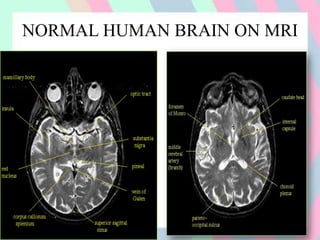

NORMAL HUMAN BRAIN ON MRI

TI WEIGHTED T2 WEIGHTED

CSF, cortical bone, air &

rapidly flowing blood have

negligible signals

appear dark

CSF has bright signal

intensity & relative to a

dark signal from grey &

white matter

Fat & bone marrow have

high signal intensity

appear white

Useful in evaluation of

cerebropontine angle,

cistern & pituitary fossa

Useful in demyelination,

edema & tumor infiltration,

to reveal brain pathology

more clearly.